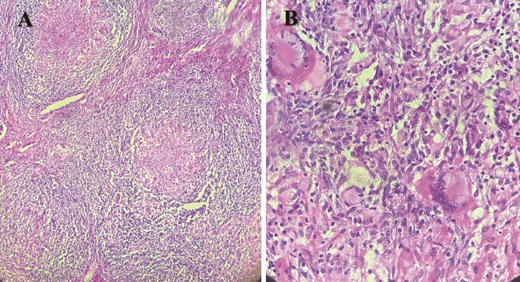

Macroscopique examination of the speciman schowed revealed inflammatory granulomatous epithelio-giganto-cellular changes with caseous necrosis, suggestive of tuberculosis (Fig. 3).

Histological images showing granulomatous inflammatory changes with epithelioid giant cells, as well as early caseous necrosis.